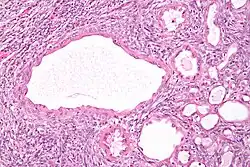

Micrograph of a cystic nephroma. H&E stain. Micrograph of a cystic nephroma. H&E stain.

The characteristics of cystic nephromas are:

- Cysts lined by a simple epithelium with a hobnail morphology, i.e. the nuclei of the cyst lining epithelium bulges into the lumen of the cysts,

- Ovarian-like stroma that has a:

- Spindle cell morphology, and has a

- Basophilic cytoplasm.